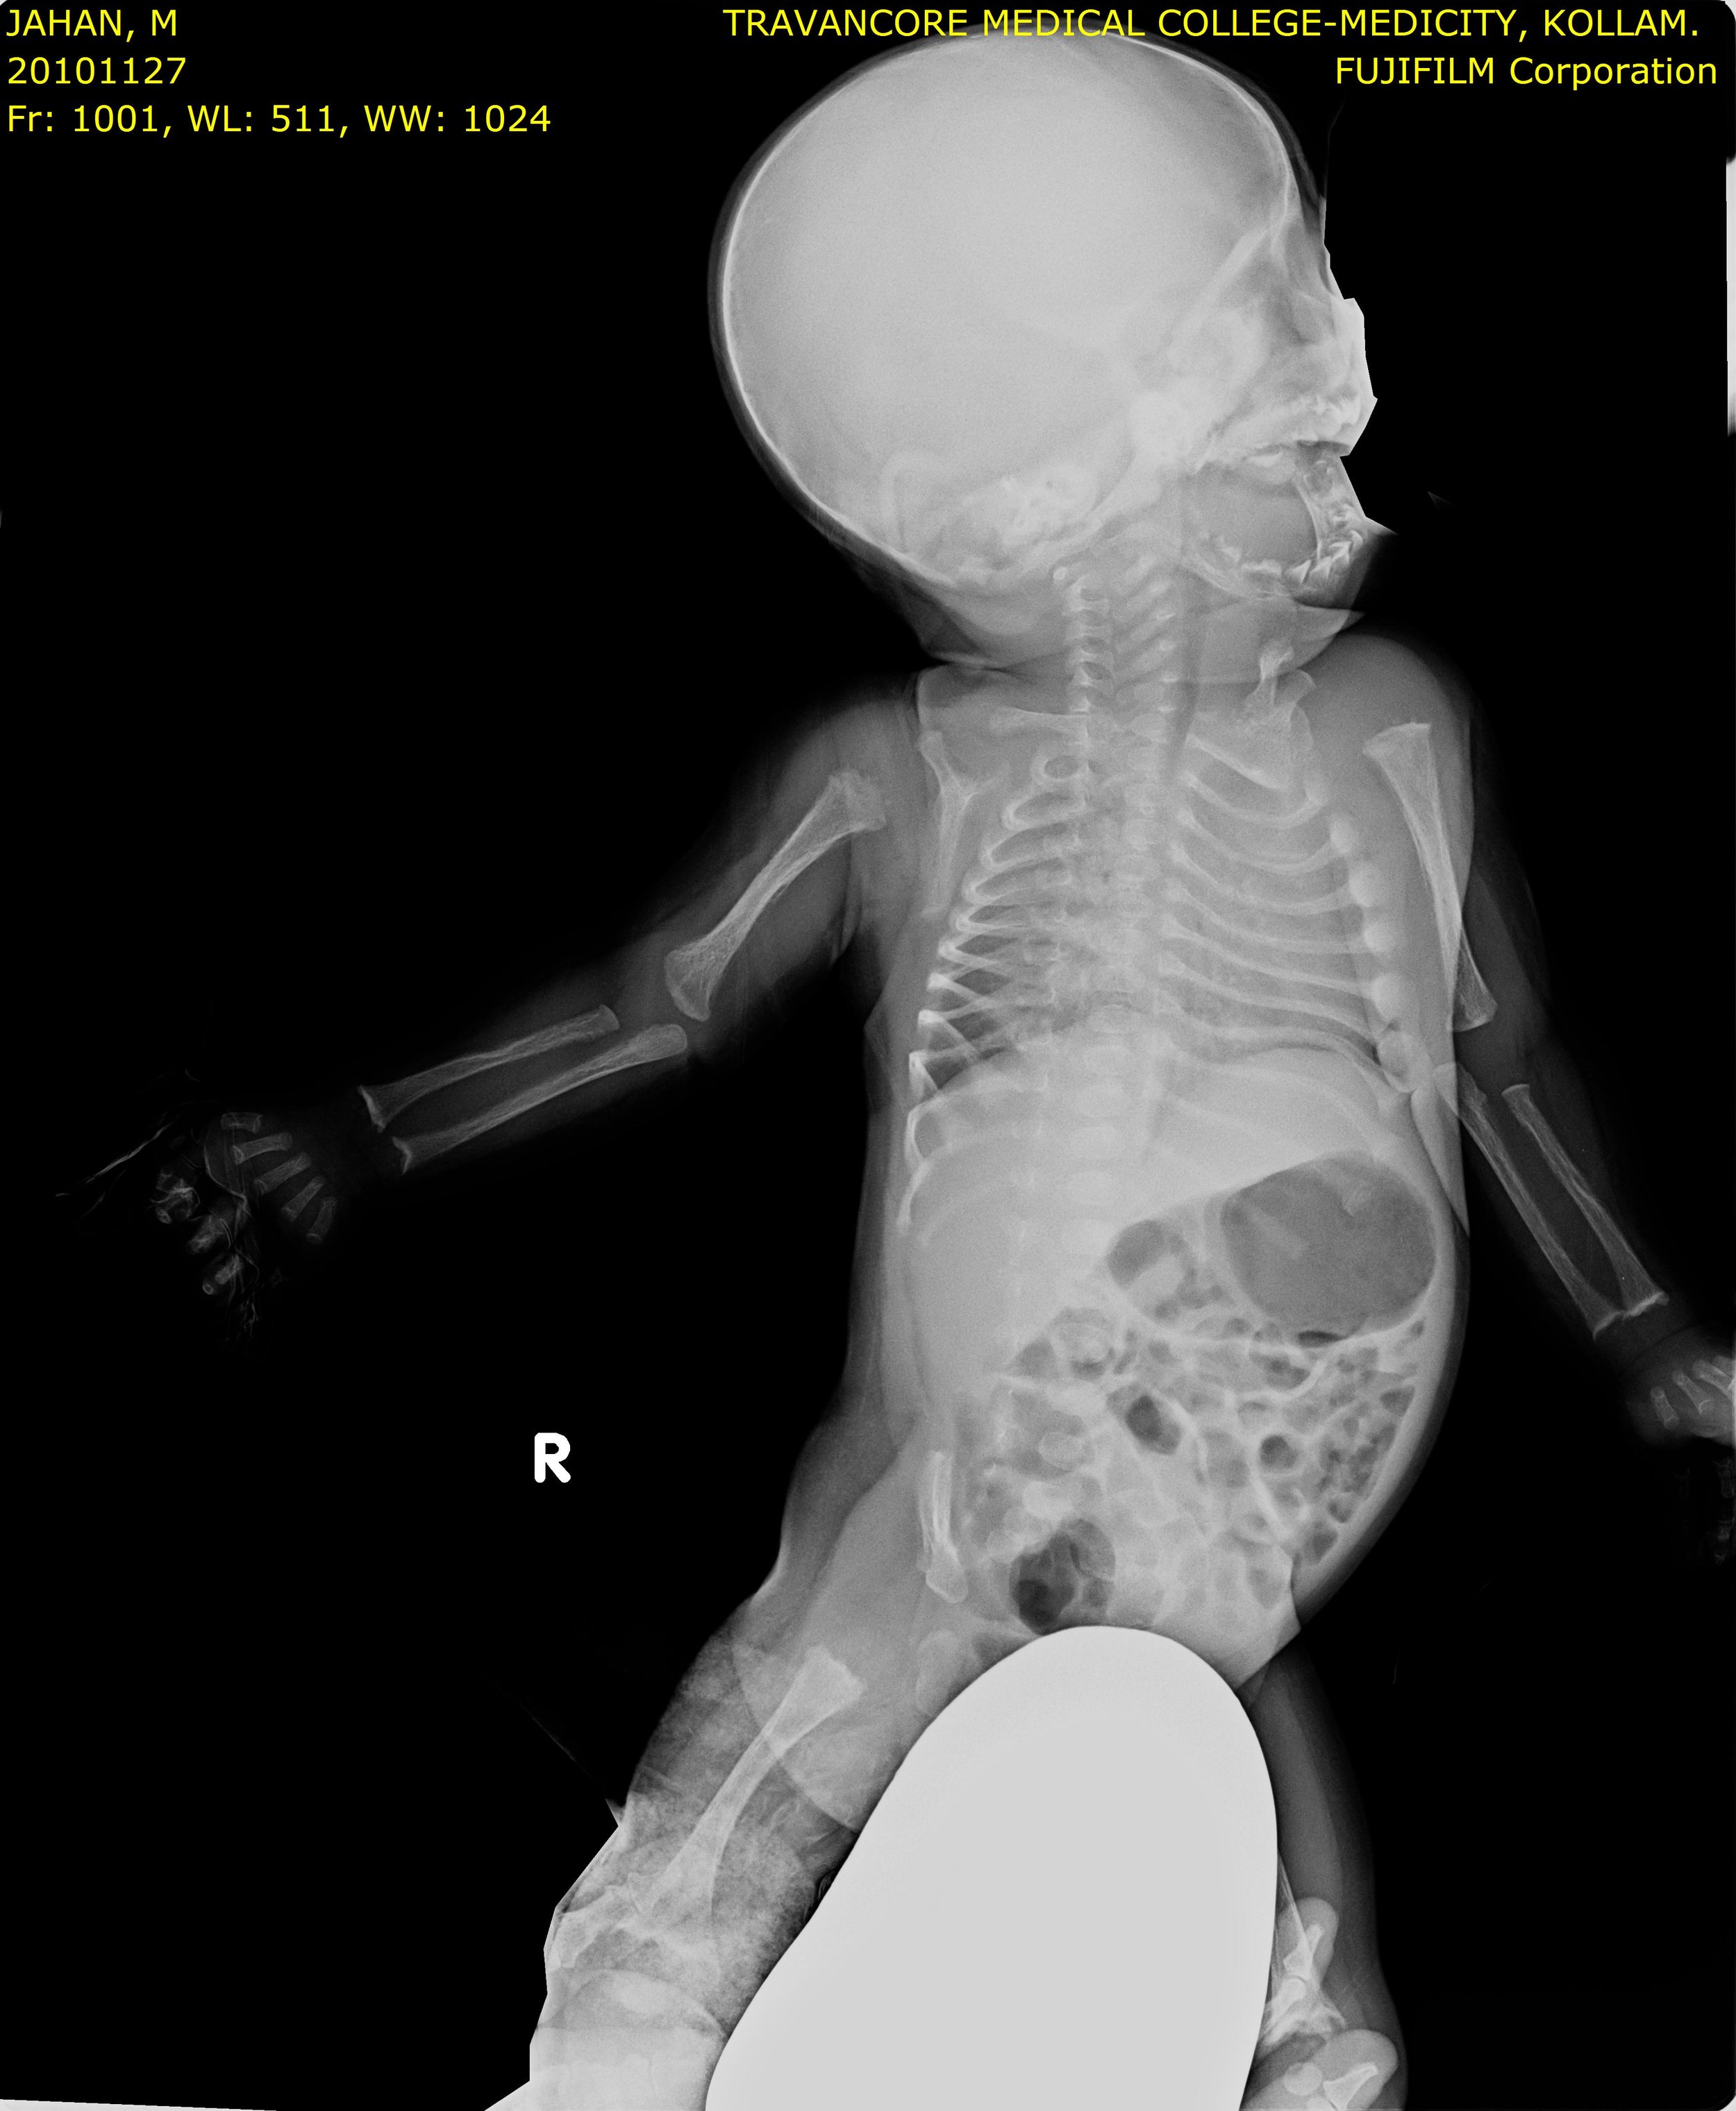

Here we share radiographic images to help with diagnosis of Jansen's disease:

Jansen's patients show extreme disorganization of the metaphyses of the long bones and of the metacarpal and metatarsal bones in sharp contrast to the almost normal appearance of the epiphyseal centers, which on x-ray appear widely separated from the long bones. The chin is receding. The fingers, especially the distal phalanges, are very short. The spine, pelvis, and lower legs are distorted.

Jansen's patients present at birth with prominent eyes, choanal stenosis, wide cranial sutures, highly arched palate, micrognathia, rib fractures, and irregularities of the metaphyses of the long bones resembling rickets. At the age of 2-3, patients show stunted growth, waddling gait, enlarged joints, prominent supraorbital ridges, and frontonasal hyperplasia.